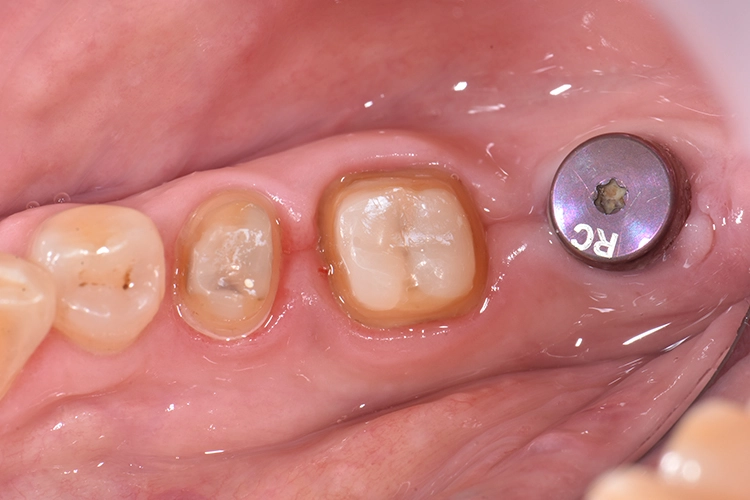

Bilder: Dr. Lampson / HannkerUm die monolithischen Restaurationen zu charakterisieren und zu glasieren, kam GC InitialTM Lustre Pastes NF zur Verwendung (Abb. 17). Nachdem die provisorischen Versorgungen entfernt waren, zeigte sich ein guter Gingiva-Zustand (Abb. 18).

Bilder: Dr. Lampson / HannkerDie Kronen für die Zähne 45 und 46 wurden mit einem selbstadhäsiven Befestigungs-Composite (G-CEM LinkAce; GC*) auf den Pfeilerzähnen angebracht, die Krone für Zahn 47 auf das Implantat geschraubt (35 Ncm) und der Zugang im unteren Bereich mit Teflon, im oberen mit Composite gefüllt (Abb. 19). Nach Überprüfung der Okklusion wurde der Patientin das Endergebnis präsentiert.